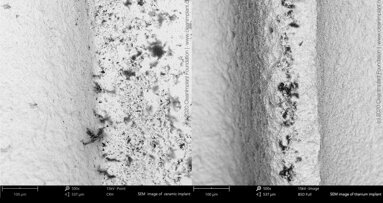

The objective of this study was to investigate the effect of sandblasted, large-grit, acid-etched (SLA) implant surfaces treated with titanium dioxide (TiO2) microparticles on the implants’ stability and resistance to reverse torque.

Six rabbits received 24 cylindrical dental implants and were placed in two groups (n = 3 per group): control group, with smooth surfaces; and test group, with the SLA surface treated with TiO2 microparticles. All of the animals were sacrificed after four weeks. Half of the implants (one per animal from each group) were used to test removal torque values and half of them were used for the histological analysis.

Reverse torque was significantly different between the groups (p = 0.0001). The histological analysis showed higher degrees of bone organization in surface samples from the test group.

Results indicate that blasting implant surfaces with TiO2 particles is an appropriate treatment option, with minimal risk of contamination by residual debris from the procedure.